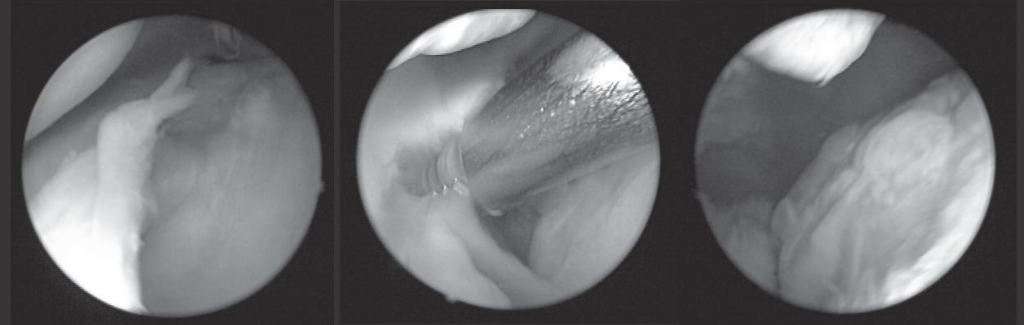

▲ 揭開隱藏病灶的面紗。左圖,